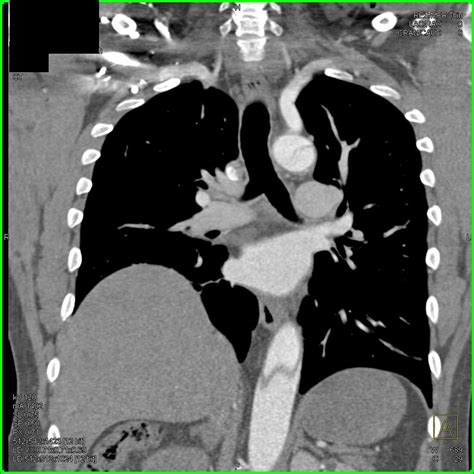

When a patient presents to the emergency room with symptoms like tearing chest pain that radiates to the back, medical teams must act with extreme precision. The diagnostic window for aortic dissection is remarkably narrow. A Aortic Dissection CT study is typically performed as a CT Angiography, which involves the intravenous administration of contrast dye. This dye highlights the vascular structures, allowing radiologists to see exactly where the blood is flowing within the aortic wall.

Why is this specific imaging modality preferred? Unlike an MRI or a transthoracic echocardiogram, a high-speed CT scan can capture images of the entire thoracic and abdominal aorta in a matter of seconds. For patients who are hemodynamically unstable, every minute counts, and the CTA provides the clarity needed to determine whether an immediate surgical intervention or aggressive medical management is required.

The time between the onset of symptoms and the final diagnostic report is the most critical period for survival. Because aortic dissection can mimic other conditions like a heart attack (myocardial infarction) or pulmonary embolism, clinicians often order a "triple rule-out" CT protocol. This specialized Aortic Dissection CT protocol covers the coronary arteries, the pulmonary arteries, and the aorta simultaneously. This comprehensive approach ensures that no time is wasted in identifying the exact cause of the patient’s distress, allowing for the correct life-saving treatment path to be initiated without delay.